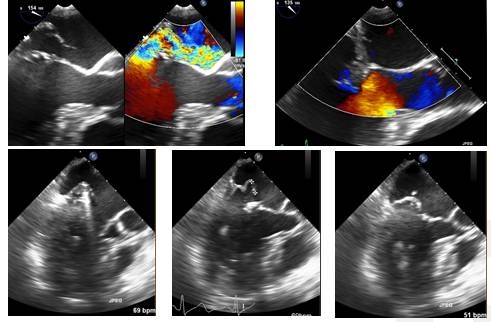

二尖瓣返流及治疗

◆退行性改变所致的退行性二尖瓣反流(Degenerative Mitral Valve Regurgitation, DMVR)是发达国家中最常见的心脏瓣膜疾病之一

◆DMVR涉及瓣膜结构和功能的一系列的变化,主要包括腱索的延长、断裂,瓣叶的增厚并最终引起瓣膜整体功能的不协调,导致二尖瓣反流的发生

◆外科手术修复腱索使用的人工腱索采用ePTFE制作,能够校正由于腱索断裂或伸长导致的二尖瓣脱垂。主要问题是创伤大、开胸、体外循环,难以准确估测所需腱索长短

Case 2